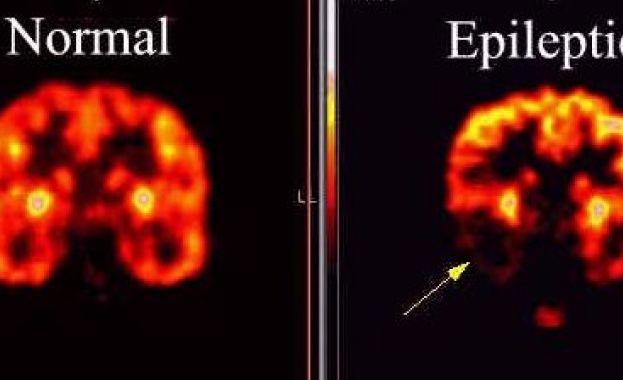

26 март е Световен ден в подкрепа на страдащите от епилепсия

/КРОСС/26 март е Световния ден за информиране на хората за епилепсията и подкрепа на страдащите от това заболяване. Денят е наречен Лилав ден. Един на всеки 20 души у нас може да получи епилептичен пристъп, а един на всеки 200 заболява от епилепсия, сочат данните.

Независимо, че епилепсията е определяна като най-често срещаното неврологично заболяване при децата, специалистите, квалифицирани да работят в тази област у нас към края на 2013-та година са 15 души. С подходящото лечение между 70% и 75% от болните могат да бъдат излекувани, съобщават от Асоциацията на родителите на деца с епилепсия.